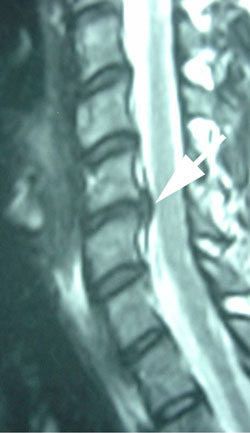

Figure 5 is a lateral MRI view of the spine shown on x-ray in Figures 1-4. At the arrow is the disc herniation, in this case at the C5-C6 level, where we see the instability and backward movement of the C5 vertebra on C6 below it. This disc herniation is also shown in Figure 6 below in an axial or cross cut view through the disc space at C5-C6 showing the disc herniation compressing the nerve to cause the arm pain that this patient complains of.  (See the large arrow.)

active inflammation in the cervical spine disc